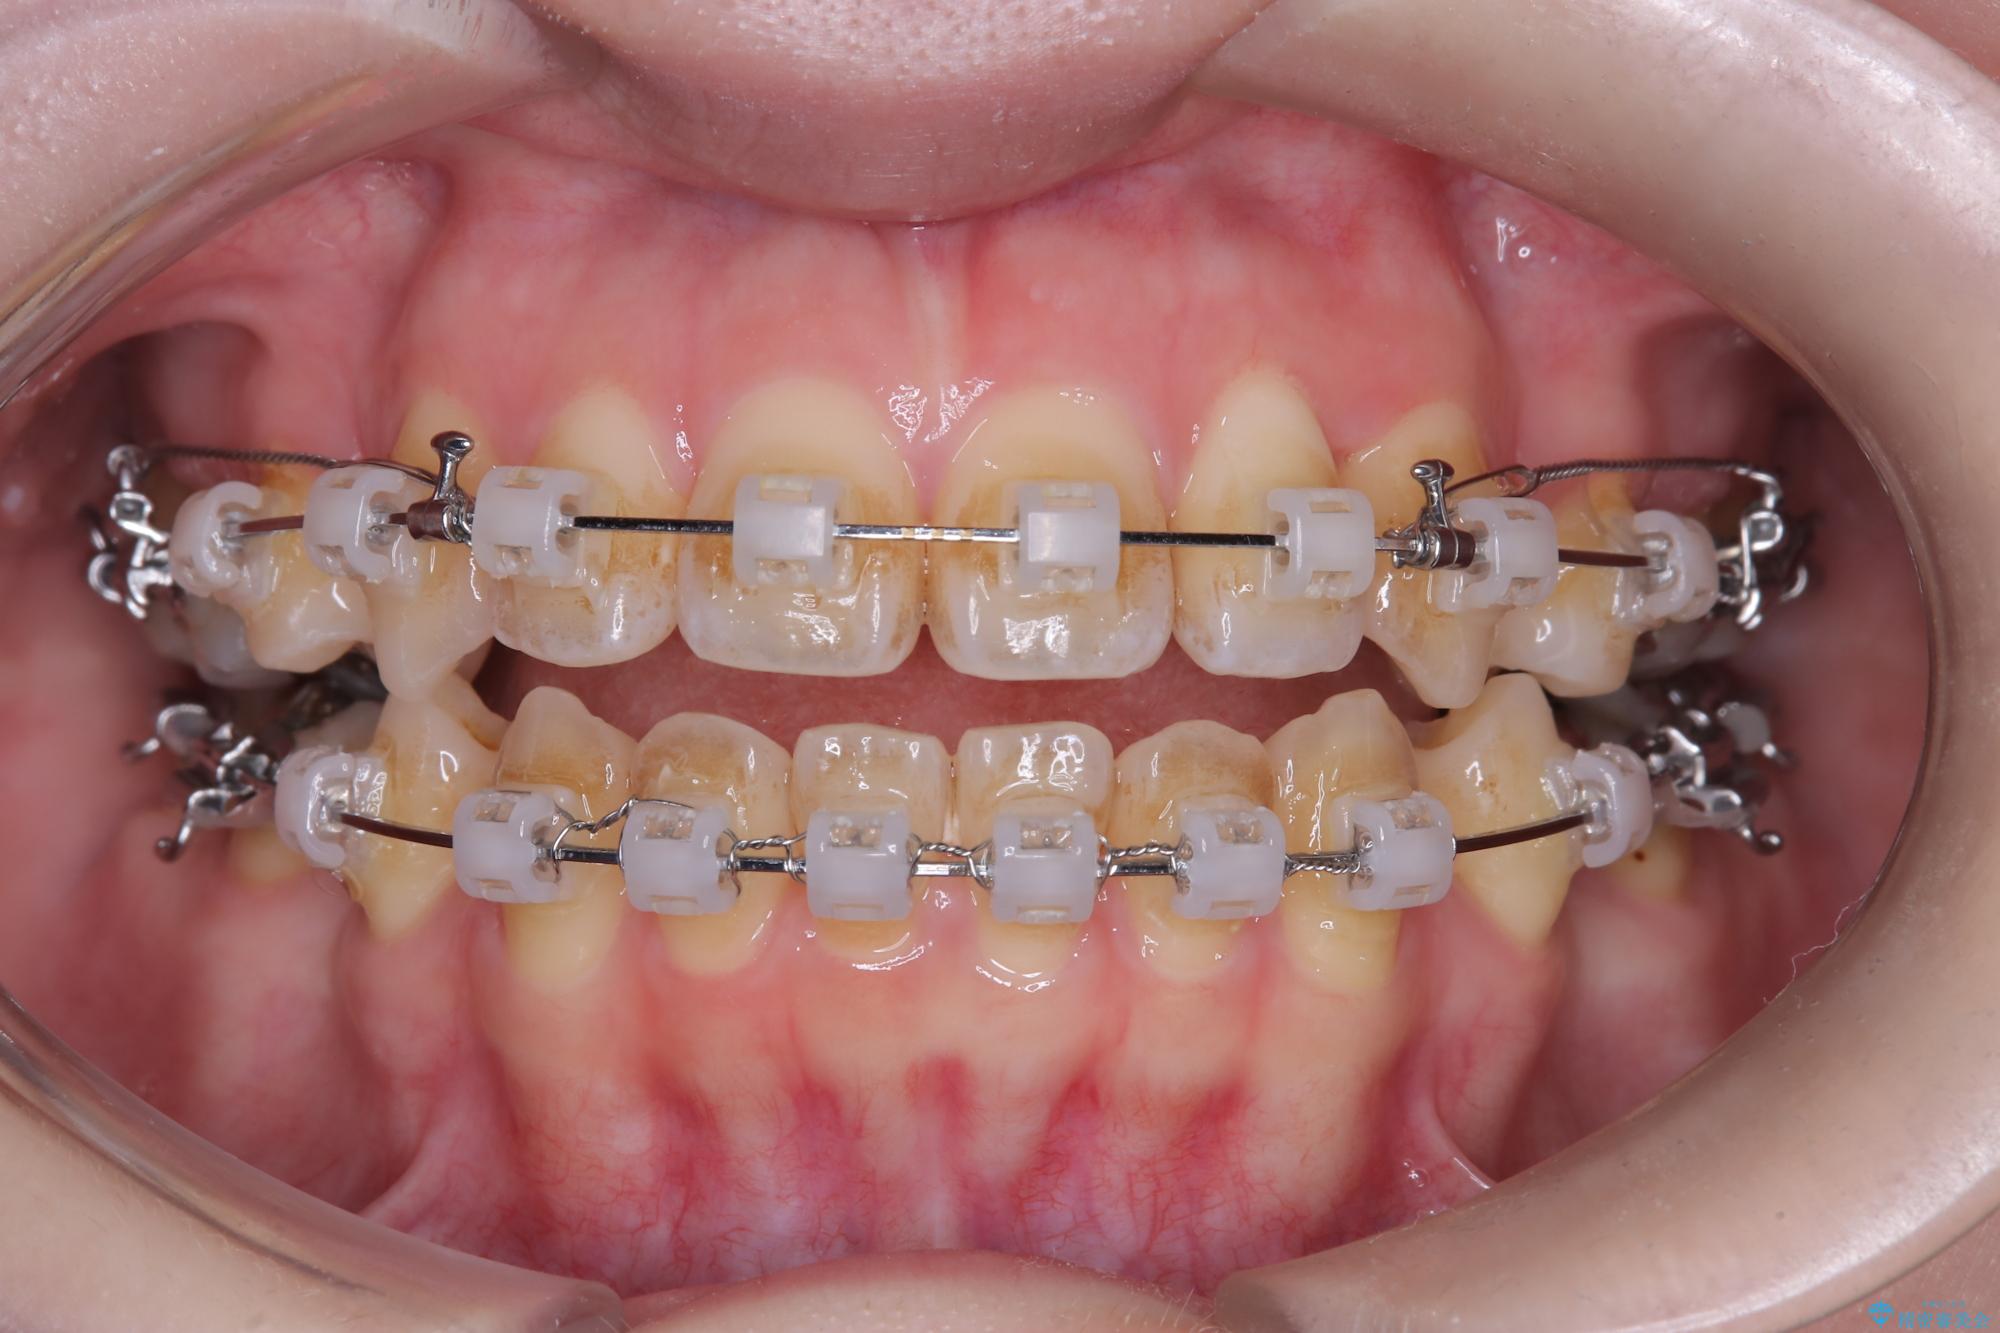

- ワイヤー矯正(クリア装置)

- 開咬と歯のデコボコ(叢生)、八重歯を主訴にご来院された患者様です。

矯正の精密検査の結果、上顎左右4番および下顎左右5番の計4本を抜歯し、ワイヤー矯正(クリア装置)にて治療を行いました。

虫歯があったので、虫歯治療は矯正前に行っています。